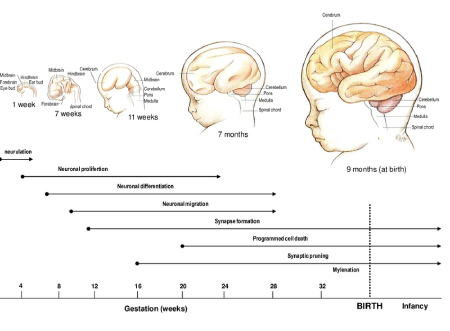

۱. رشد مغز نوزاد: یک فرآیند پیچیده و سریع

رشد مغز نوزاد از آغاز بارداری، یعنی از لحظه باروری، شروع میشود. در اوایل بارداری، سلولهای عصبی (نورونها) به سرعت تقسیم شده و در مراحل بعدی شروع به اتصال به یکدیگر میکنند. در این زمان، مغز نوزاد هنوز به اندازه یک دانه برنج است، اما شروع به ایجاد مسیرهای عصبی میکند که بعدها به مهارتهای مختلف مانند حرکت، زبان، و حافظه تبدیل خواهند شد.

در سه ماهه اول بارداری:

ساختار مغز در حال شکلگیری است و شروع به تشکیل قسمتهای مختلف خود میکند.

نورونها به سرعت در حال تقسیم و تشکیل اتصالات عصبی هستند.

در این مرحله، مغز نوزاد به طور کلی هنوز نمیتواند عملکردهای پیچیدهای انجام دهد، اما یک سری فعالیتهای ساده مانند حرکتهای ابتدایی عضلانی آغاز میشود.

در سه ماهه دوم بارداری:

مغز نوزاد شروع به فعالیتهای پیچیدهتری میکند. سیستم عصبی به شدت در حال گسترش است و این دوره یکی از مهمترین مراحل رشد مغز محسوب میشود.

در این مرحله، نوزاد قادر به انجام حرکتهای ابتدایی مانند تکان دادن دستها و پاها است.

سیستم شنوایی نوزاد در حال تکامل است و او شروع به شنیدن صداها از محیط اطراف، از جمله صدای ضربان قلب مادر و صدای محیط بیرونی، میکند.

در سه ماهه سوم بارداری:

مغز نوزاد به سرعت در حال رشد و تکامل است. در این دوره، بخشهایی از مغز که مسئول مهارتهای حرکتی، حافظه، و احساسات هستند، فعالیت بیشتری از خود نشان میدهند.

نوزاد شروع به واکنش نشان دادن به محرکهای بیرونی مانند نور و صدا میکند.

نوزاد قادر است چشمان خود را باز و بسته کند، به اطراف حرکت کند و در برخی موارد حتی مکیدن را آغاز کند.

۳. ارتباطات مغزی: تمرینات اولیه مغز نوزاد

شاید جالب باشد که بدانید مغز نوزاد حتی قبل از تولد به طور فعال در حال برقراری ارتباطات عصبی است. این ارتباطات در آینده به پایههای یادگیری، حافظه و مهارتهای مختلف تبدیل میشوند.

۴. رشد شناختی قبل از تولد

یکی از شگفتانگیزترین جنبههای رشد مغز نوزاد، توانایی او در یادگیری و ثبت خاطرات اولیه است. حتی قبل از تولد، نوزاد میتواند به برخی از تجربیات محیطی واکنش نشان دهد.